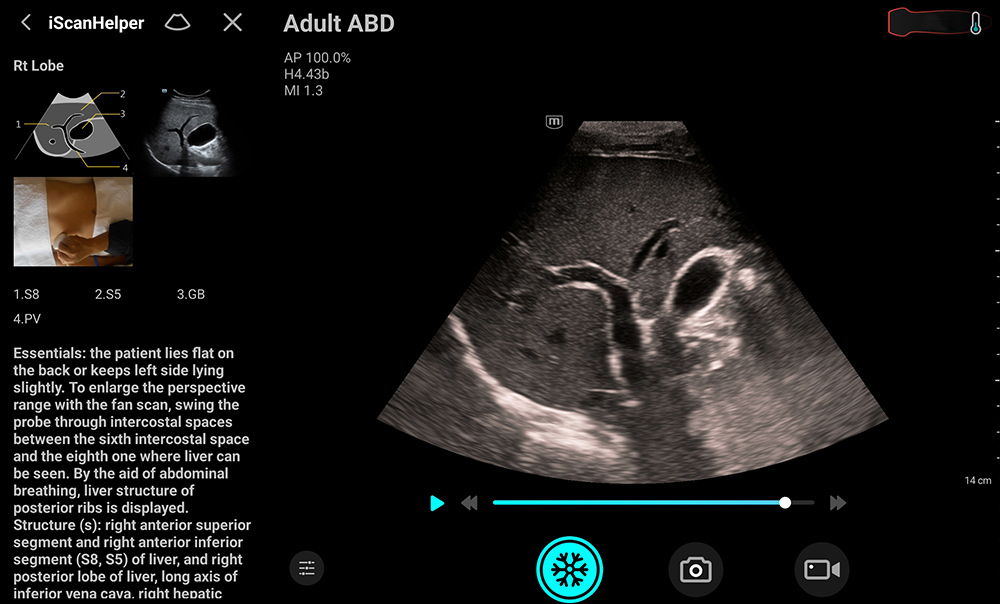

Detecteert automatisch de anatomie en schakelt tussen voorinstellingen voor de buik, schildklier en halsslagader en optimaliseert deze. Doordat er zo aanzienlijk minder handmatige aanpassingen zijn vereist, wordt scannen eenvoudiger.